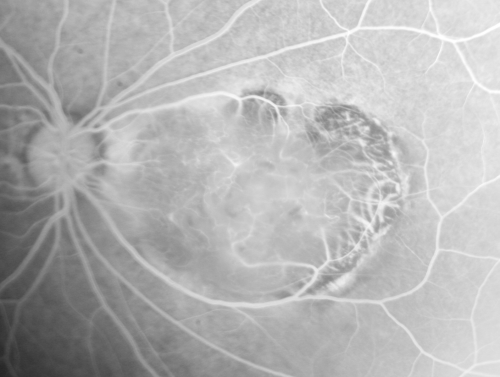

Retinocytoma - Retinoma - Regressed Retinoblastoma 43 year old male incidental finding

Retinocytoma - Regressed Retinoblastoma - Retinoma